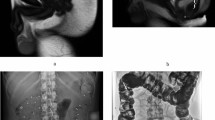

The ultrasound assessment was performed according to the current guideline and regulations. The TLUS was performed with patients in the lithotomy position. An abdominal 3-D probe was then placed on the perineum or at the labia with gentle pressure. The bladder was half-filled, and the rectum might be instilled with ultrasound gel. Images were acquired at rest, with contraction and maximal straining13. Data of ultrasound volume were blindly analyzed at a later date by the author on a desktop PC using the proprietary software 4D View v 10 (GE Kretz Medizintechnik). POP was determined relative to the posteroinferior margin of the pubic symphysis using volume data acquired on maximum Valsalva, such as in the ultrasound volume demonstrating the most marked POP14. An enterocele was diagnosed when the lower margin of the small bowel or omentum reached or was below the pubic bone. A true rectocele was defined as the presence of a discontinuity in the anterior contour of the internal anal sphincter and anterior anorectal muscularis, resulting in a diverticulum of the ampulla, indicative of a defect of the recto-vaginal septum (RVS)4. If substantial downwards displacement of the rectal ampulla was seen on image (at least 15 mm below the pubic symphysis) without an actual rectocele, perineal hyper-mobility was diagnosed15. Figure 1 illustrates the ultrasound diagnosis of rectocele.

Figures a and b showed the location of the rectum (R) in resting and Valsalva states, respectively. The yellow line refers to the horizontal line from the lower margin of pubis. The green line represents the extended ventral line of internal sphincter. The depth of rectocele was measured by the distance from the farthest point of the ampulla to the extended ventral line of internal sphincter. The rectocele was diagnosed as the discontinuity in the ventral contour of the anorectal muscularis.